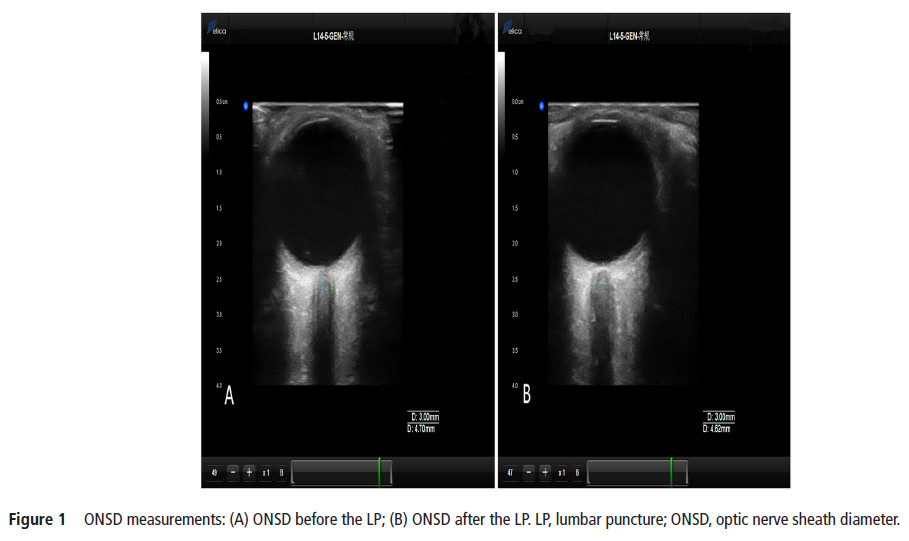

The current study aimed to identify whether ultrasonographic measurements of optic nerve sheath diameter (ONSD) could dynamically and sensitively evaluate real-time intracranial pressure (ICP). ONSD

measurements were performed approximately 5 min prior to and after a lumbar puncture (LP). A total of 84 patients (mean±SD age, 43.5±14.7 years; 41 (49%) men; 18 patients with elevated ICP) were included in the study. The Spearman correlation coefficients between the two observers were 0.779 and 0.703 in the transverse section and 0.751 and 0.788 in the vertical section for the left and right eyes, respectively. The median (IQR) change in ONSD (ΔONSD) and change in ICP (ΔICP) were 0.11 (0.05–0.21) mm and 30 (20–40) mmH2O, respectively, for all participants. With a reduction in cerebrospinal fluid pressure, 80 subjects (95%) showed an immediate drop in ONSD; the median (IQR) decreased from 4.13 (4.02–4.38) mm to 4.02 (3.90–4.23) mm (p<0.001). Significant correlations were found between ONSD and ICP before LPs (r=0.482, p<0.01) and between ΔONSD and ΔICP (r=0.451, p<0.01). Ultrasonic measurement of ONSD can reflect the relative real-time changes in ICP.【The ONSD was measured with the Delica MVU-6300 (Shenzhen, Guangzhou, China),】

【作者注:腰穿前后對(duì)比視神經(jīng)鞘變化,發(fā)現(xiàn)超聲檢測(cè)視神經(jīng)鞘直徑可以實(shí)時(shí)顯示顱內(nèi)壓改變,也進(jìn)一步證實(shí)了關(guān)于視神經(jīng)鞘研究的規(guī)范操作流程,應(yīng)該在腰穿之前進(jìn)行視神經(jīng)鞘測(cè)量】。